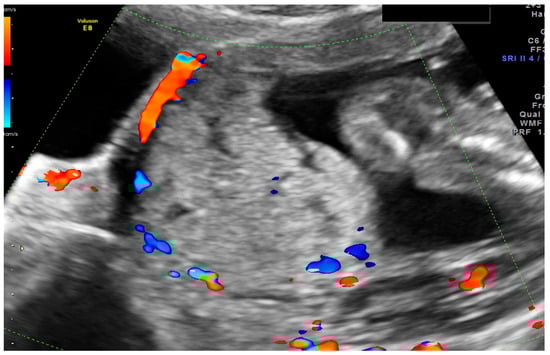

1.1. Case 1

1.2. Case 2